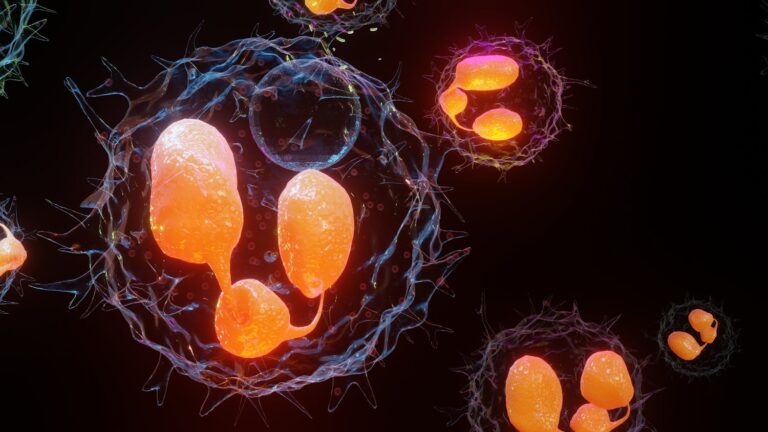

Quand nos cellules font le ménage : zoom sur la phagocytose

Chaque seconde, notre corps combat des envahisseurs invisibles grâce à des cellules qui les “mangent” littéralement pour nous protéger. C’est ce qu’on appelle la phagocytose. Découvrez ce mécanisme vital et fascinant ! Chaque seconde, notre corps combat des envahisseurs invisibles grâce…